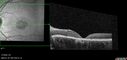

25 year old with Stargard and 2 ABCA4 mutations.vu 192 foisShe has worn glasses since she was a kid. Since she became an adult her vision started to deteriorate more rapidly. This seems to have been happening since she entered the accounting department for the last two years. Her vision is worse in the light especially when she is driving. She can see green lights in the night but not in the day. She sees better on a dark background than on a light background. Her mom is genetically visually impaired with Stargardts. Her father has RP. The mother was genetically tested in Boston about 23 years ago. That was when the gene was first being isolated. (The mother has seven brothers and sisters and four have stargardts and they are legally blind. Also one cousin has it.)

VA OD: Dcc20/160-1 PH20/80 Ncc20/200-2

VA OS: Dcc20/160-2 PH20/80-1 Ncc20/200-1

IOP: TP: OD:20 OS:21